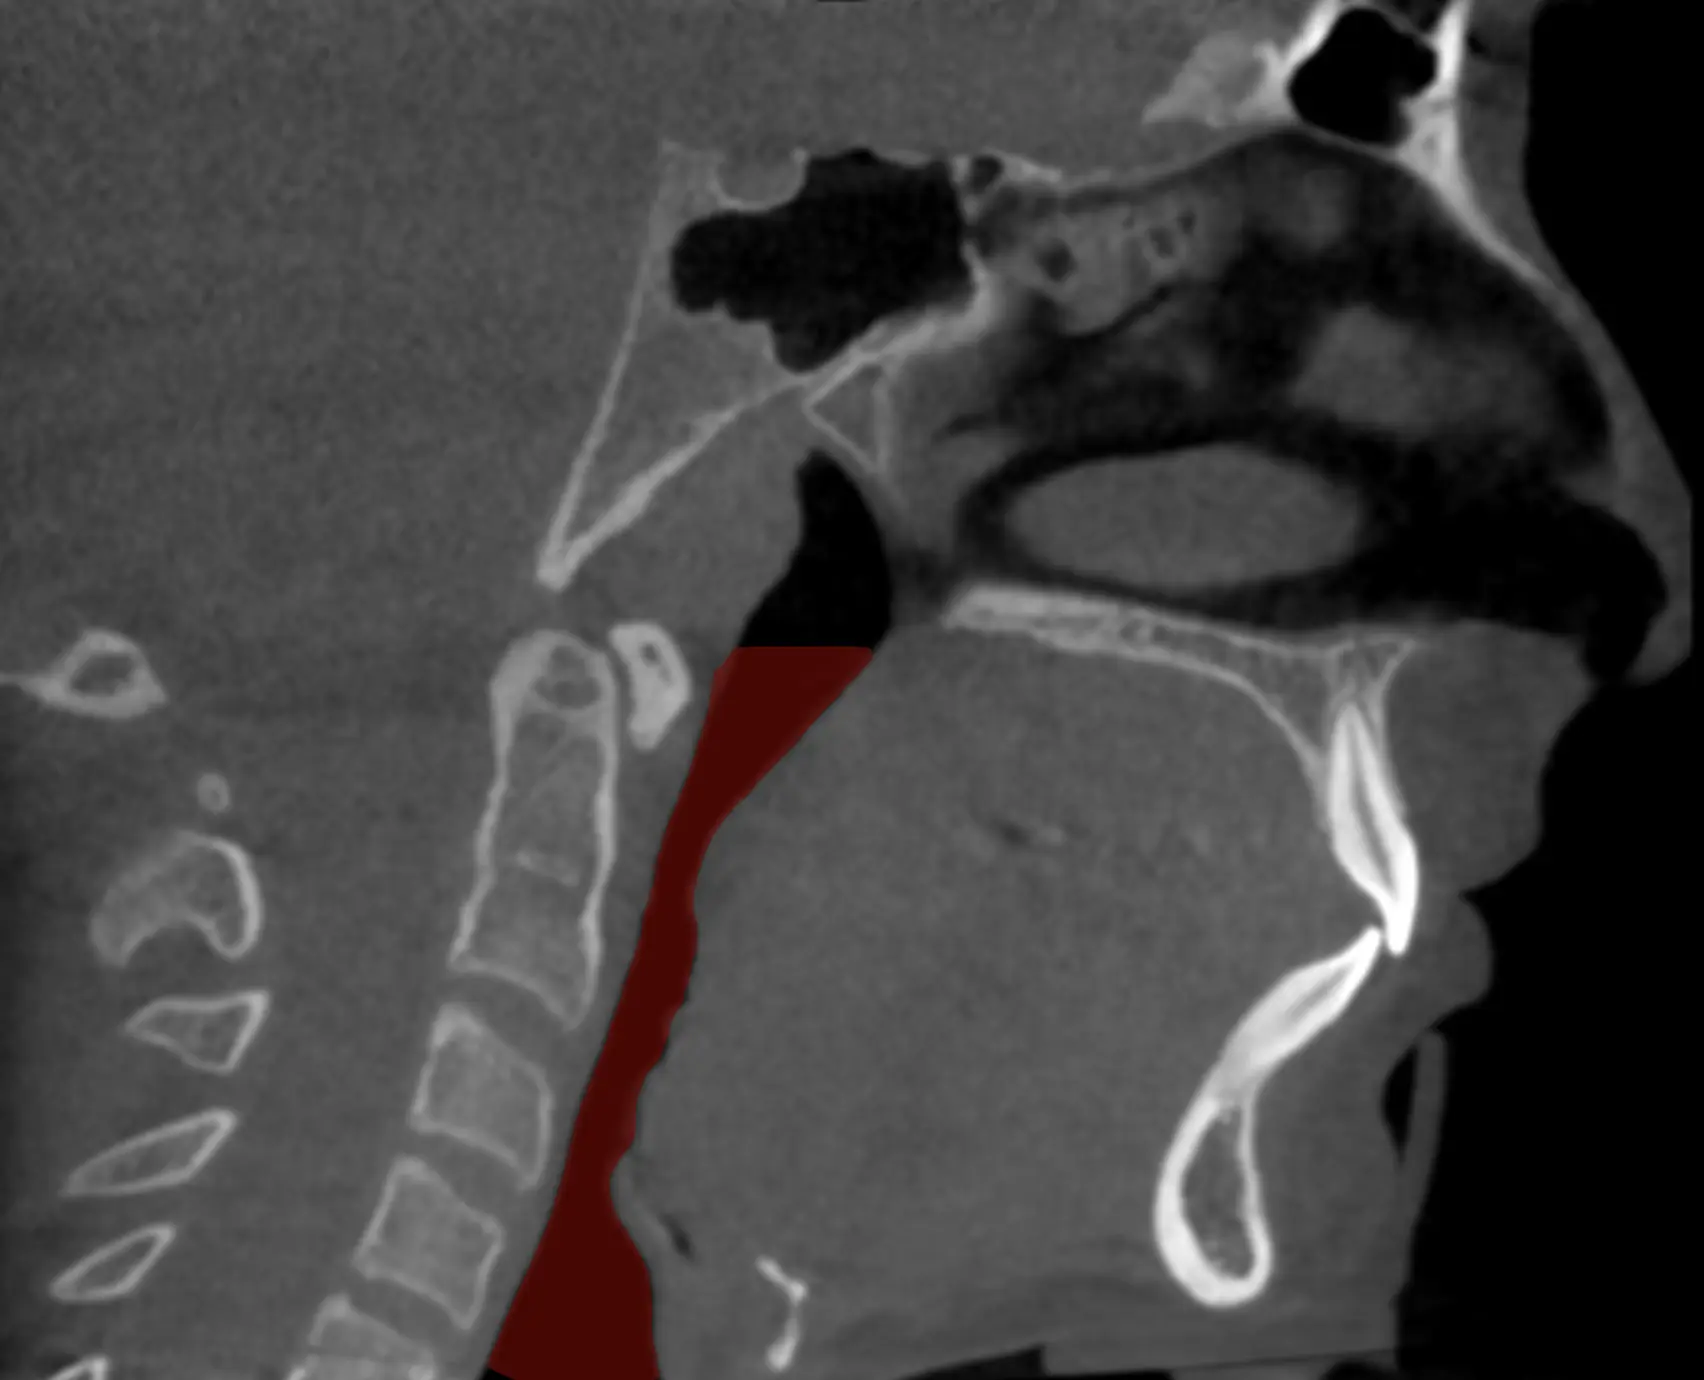

Il est important de noter que la chirurgie n'est généralement pas la première option de traitement pour l'AOS et est souvent considérée lorsque d'autres traitements, tels que la ventilation spontanée avec pression expiratoire positive (CPAP) ou les dispositifs d'avancement mandibulaire, n'ont pas été efficaces ou tolérés. Avant de recommander une intervention chirurgicale, le chirurgien maxillo-facial effectuera une évaluation minutieuse de votre condition ainsi que de votre profil squelettique afin de déterminer si vous êtes effectivement candidat à la chirurgie. Bien souvent une anomalie ou un manque de projection des mâchoires peut avoir un impact significatif sur le volume des voies respiratoires supérieures. Un avancement maxillo-mandibulaire peut dès lors être considéré. Cette chirurgie pratiquée par les chirurgiens maxillo-faciaux améliore significativement les dimensions et la stabilité des voies aériennes pharyngées en plus d'être associée à un repositionnement antérieur des muscles suprahyoïdiens. L'analyse des changements morphologiques à l'aide d'une tomodensitométrie après la chirurgie d'avancement du complexe maxillo-mandibulaire montre un élargissement significatif des dimensions latérale et antéro-postérieure des voies respiratoires pour une grande majorité de patients.